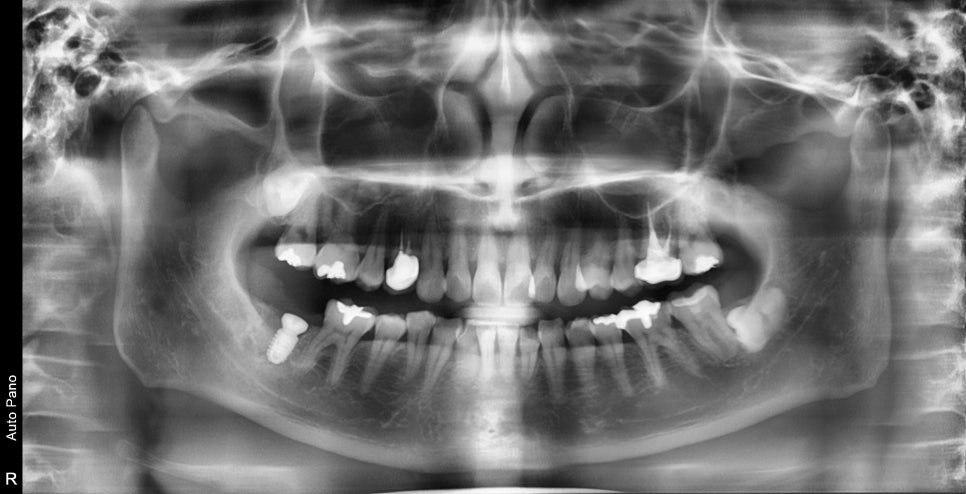

2달 후 사진입니다.

치조골 이식술을 한곳이 의도한 바와 같이 아주 잘 아물었습니다.

치유도 좋고 임플란트의 고정 성도 좋아서 바로 보철 단계를 진행했습니다.

아직 치조골 이식술 한 공간의 강도는 아직 주변 뼈처럼 강하진 않지만

임플란트를 지지해줄 정도의 강도가 되었고

시간이 지남에 따라 주변 치조골로 대체가 될 것입니다.